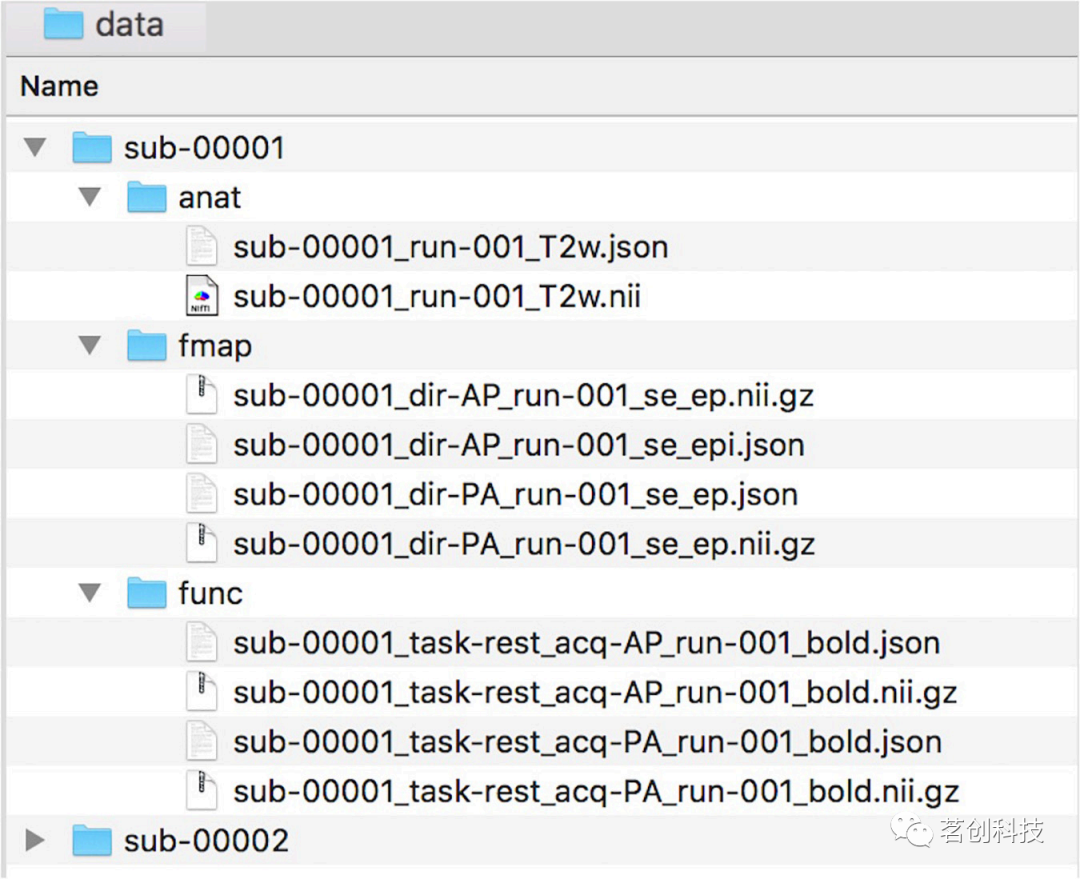

数据结构

NeoRS使用https://bids.neuroimaging.io/中所述的脑成像数据结构(BIDS)格式。有关NeoRS的数据命名和编排示例,见图1。

图1.NeoRS的数据命名和编排示例。